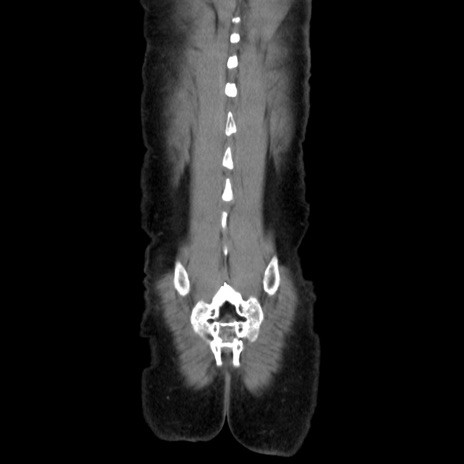

症例37(冠状断像)

【症例】40歳代 男性

【主訴】腹痛

【現病歴】4時間ほど前に電車に乗車中に臍部上より腹痛出現。徐々に増悪し起立困難となり、救急外来受診。生ものは数日食べていない。今朝お雑煮を食べた。

【身体所見】BT 36.8℃、BP 117/84mmHg、HR 91/min、SpO2 97%、苦悶様、腹部:臍上部広範囲圧痛あり、反跳痛±

【データ】WBC 8100、CRP 0.03